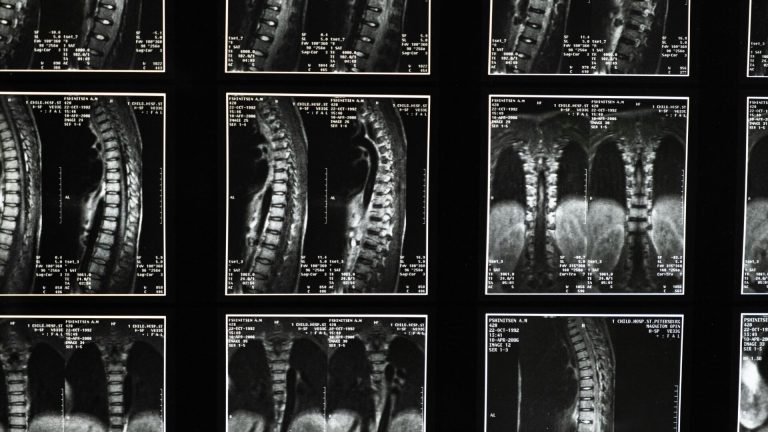

O procedimento da Universidade de Tel Aviv visa substituir a parte danificada por uma medula espinhal cultivada em laboratório que se funde com o tecido saudável acima e abaixo da lesão.

O projeto inovador, liderado por Tal Dvir, começou há cerca de três anos, quando o laboratório do professor fez a projeção de uma medula espinhal humana tridimensional personalizada em laboratório.